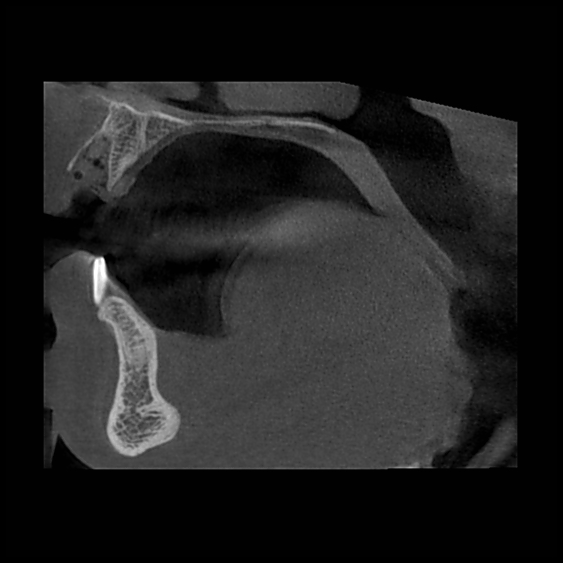

Томография зубов будет сохранена у лечащего врача, а копию передают пациенту. Врач может назначить полное обследование височно-челюстной зоны или уделить пристальное внимание определенному зубу, если выявлена определенная проблематика.

На основе томографии создают объемную модель результатов имплантации, чтобы учесть все факторы и анатомические особенности. Пациент сможет наперед увидеть, какой результат его ждет после проведения всех манипуляций.

В отличие от рентгена, где изображение получается плоским, 3Д-модель врач может повернуть под любым углом, чтобы увидеть все детали. А главное, здесь отсутствуют искажения и помехи, которые могут повлиять на результат лечения.